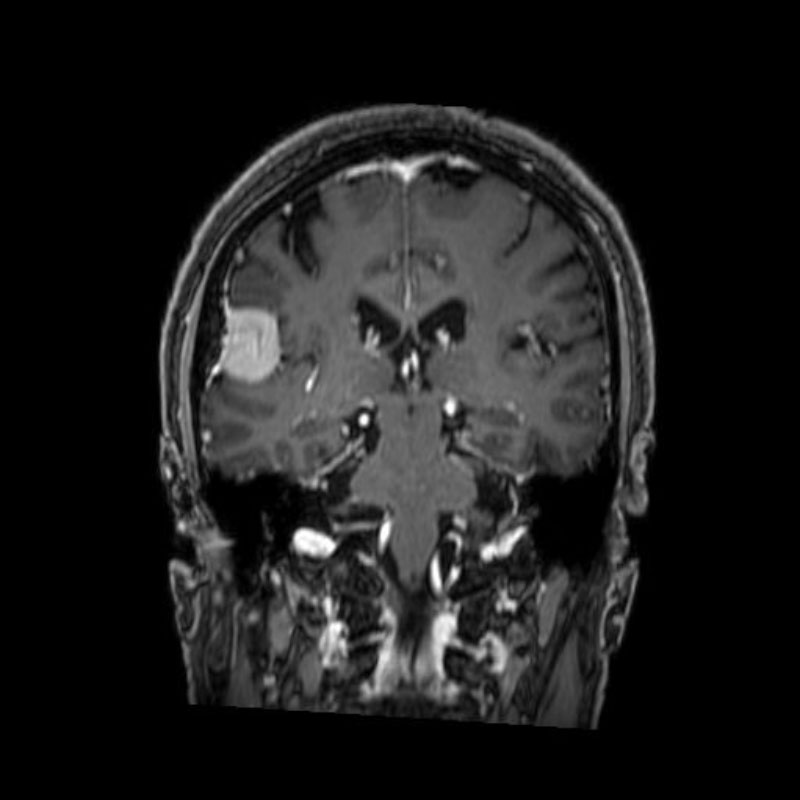

右頭頂葉腫瘍

頭蓋内腫瘍摘出術

No.’25_108 手術前1

No.’25_108 手術前2